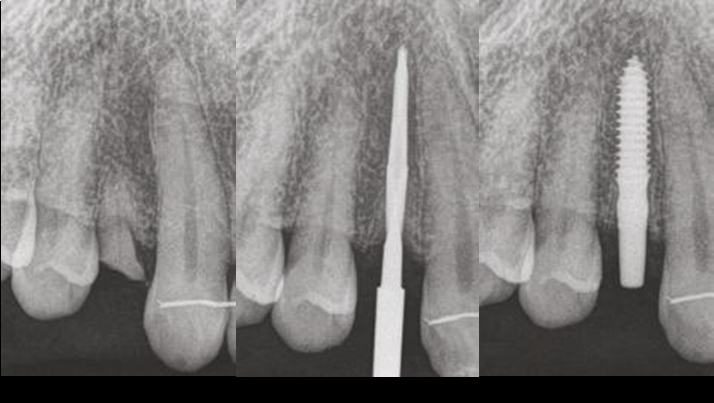

Clinical case: BPET PREDICTABILITY - State-of-the-Art SOCKET SHIELD

- Courtesy of Dr. Howard Gluckman, South Africa -

“AnyRidge is perfect for the anterior esthetic zone due to its strong initial stability & fast osseointegration.

Plus, KnifeThread® ensures space maintenance when using the PET/Socket Shield/Root Membrane Technique, showing excellent bone growth.”